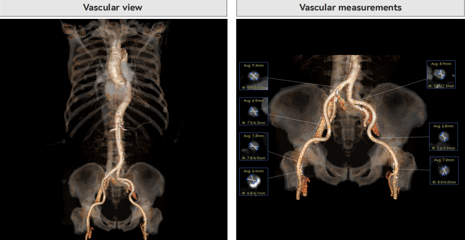

病例概览

患者病史 体检发现心脏瓣膜病半月余,平素无症状 ,有高血压病史。 后来院复查诊断为:主动脉瓣狭窄(重度)、先天性主动脉瓣二叶瓣畸形、心室肥厚、升主动脉扩张心功能 I 级(NYHA 分级)、高血压病 2 级(极高危)。 术前 CT:Type0型二叶瓣,瓣叶增厚,无钙化,类风湿性;瓣环径25.6mm,LVOT稍收窄,瓣环水平夹角66.6°,轻微横位心;左右冠开口高度可,瓣叶不长,无冠脉风险;心室收缩末内径约32mm,室壁增厚;外周入路无明显迂曲,无钙化、双侧内径可、双股中分叉,右侧为主入路能够支持20F大鞘通过。 造影角度及入路:LAO 6° CAU 13° 手术策略 采用右侧股动脉为主入路,左侧为辅助入路,常规穿刺。推荐使用20球囊预扩,预装TAV29瓣膜,初始定位对齐瓣环上0mm开始释放。 手术过程 20号球囊预扩无明显腰征 输送器过弓跨瓣顺滑 80%工作位观察 术后造影,瓣膜释放位置良好,无瓣周漏 术后超声:人工生物瓣释放后形态满意,瓣叶开放、关闭活动良好,无瓣周漏;跨瓣血流速度降至 2.5m/s,平均压力梯度6mmHg,符合手术预期。 Prostyle A®预装干瓣——“刚柔并济”助力临床最优化解决方案: 丝滑过弓能力:Prostyle A®短瓣架设计联合远端超滑亲水涂层,即使没有联合使用snare,都可以柔顺过弓,该例横位心的患者更好的展现了输送系统的柔顺性; 平衡的径向支撑力:该例患者Type0型二叶瓣,术后形态展开良好且无瓣周漏,在横位心等复杂情况下实现稳定锚定。 80%可回收设计:80%工作位观察,起搏时间更短,对患者损伤减少到最小,也利于术中精准调整瓣膜位置,保证术后效果。